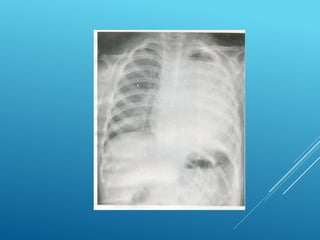

HEMOTÓRAX DERECHO

HEMONEUMOtórax

HEMOTÓRAX

Masivo

Más de 1500 ml de sangre en cavidad o más de 200ml/hora